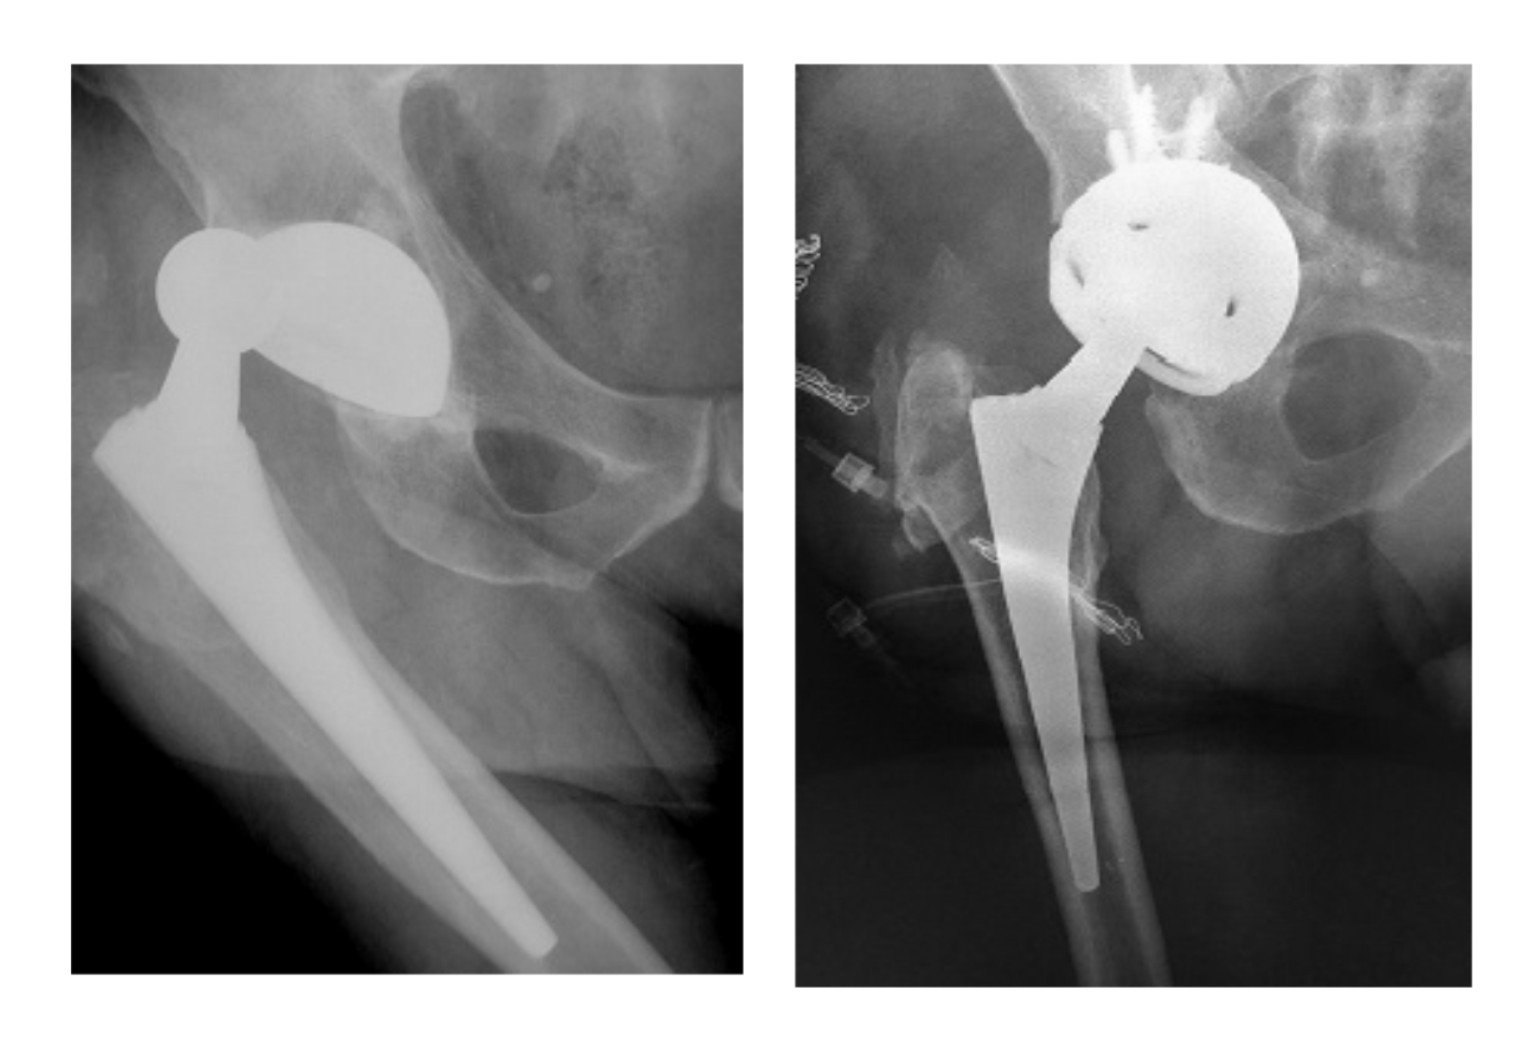

Στην εικόνα 2 ασθενής με πολλαπλά επεισόδια εξαρθρήματος και μία επέμβαση αναθεώρησης χωρίς επιτυχία ήδη στο ιστορικό του. Αιτία, δεν ήταν η κακή τοποθέτηση όπως αρχικά είχε θεωρηθεί, αλλά νευρομυικό πρόβλημα. Αντιμετωπίσαμε την κατάσταση με αναθεώρηση, χρησιμοποιώντας μια ειδικού τύπου κοτύλη, “κλειδούμενη”. Ο ασθενής έζησε άλλα 7 χρόνια μετά την επέμβαση,  με πλήρη δραστηριότητα, χωρίς να υποστεί ξανά εξάρθρημα